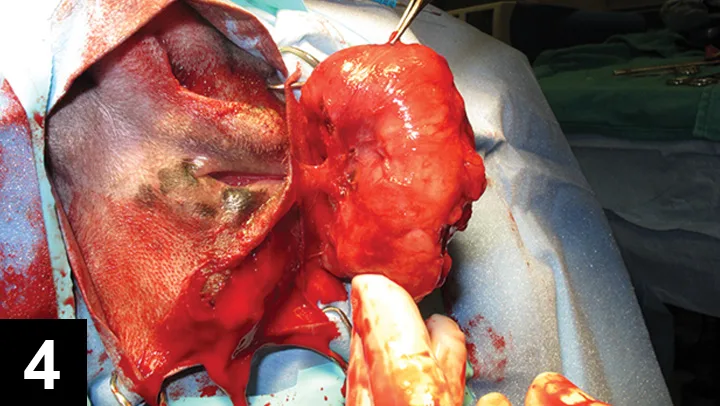

Featured Image

Figure 4

Closed anal sacculectomy for excision of the AGASAC.

Closed sacculectomy was selected (Figure 4), as an open approach is not recommended because it can result in tumor seeding of the perianal space and increase the risk for local tumor recurrence.